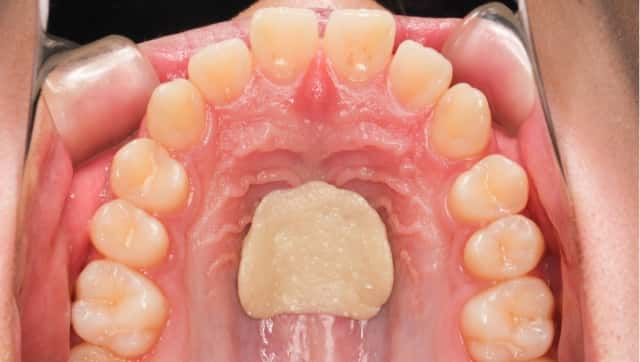

ガムを上あごに押しつける練習

![スポット]()

-

スポット

舌尖の正しい位置を覚える